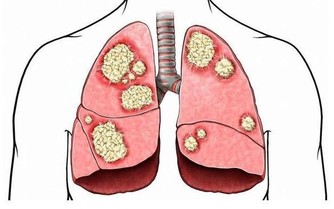

維生素的缺乏會給人體造成極大的損害,但是,如果體內維生素含量過高,同樣會引起大問題。如果維生素失調嚴重,還可能導致嚴重的疾病或中毒。

維生素D,如果攝入過量的話會出現噁心、腹瀉,還有多髒器點狀鈣化、骨骼疼痛等中毒症狀。